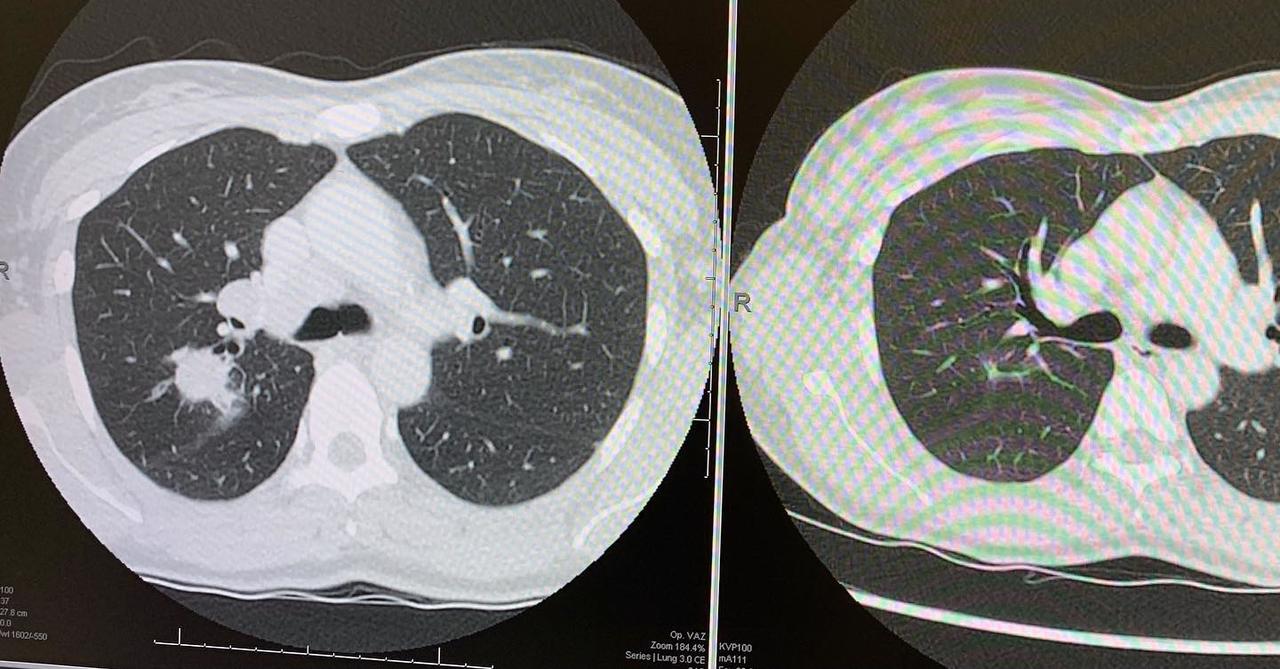

I wanted to check in with you all to again say thank you and also to share that my treatment is working 🙌🏼. You can see on the image the CT scan before (left) and after 8 weeks of chemotherapy treatment 💥. The lymph nodes in my neck and my chest are all massively reduced too💥💥